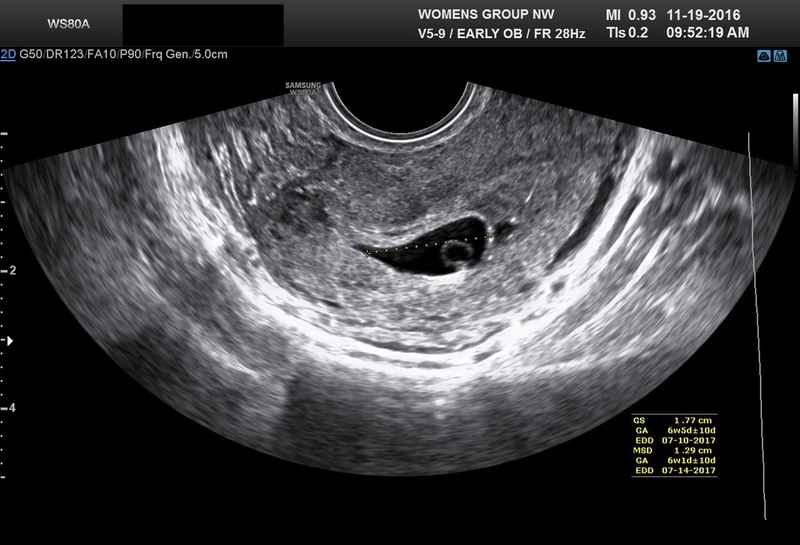

Thông thường, túi ối có hình bầu dục hoặc hình tròn. Tuy nhiên, nhiều mẹ bầu sau khi siêu âm thai được bác sĩ thông báo đang gặp phải hiện tượng túi ối méo. Điều này gây ra nhiều nỗi hoang mang và lo lắng cho thai phụ. Vậy tình trạng túi ối méo có nguy hiểm không?

Túi ối méo là một hiện tượng bất thường trong thai kỳ và gây ra nhiều lo lắng cho mẹ bầu. Vậy túi ối méo có nguy hiểm cho thai phụ và thai nhi không? Tình trạng này có khắc phục được không? Bài viết dưới đây Nhà thuốc Long Châu sẽ giúp bạn đọc giải đáp các vấn đề trên nhé!

Túi ối (túi thai) là một bọc có chứa chất mỏng nằm trong tử cung có tác dụng bao bọc và nuôi dưỡng thai nhi trong suốt thai kỳ khi bé còn nằm trong bụng mẹ.

Túi ối méo là hiện tượng túi ối có hình dạng méo mó và có dịch ở phía dưới lớp màng đệm. Túi ối méo được xem là một biểu hiện cho thấy thai nhi đang phát triển bất thường? Vậy túi ối méo có gây nguy hiểm cho mẹ và thai nhi không?

Trong một số trường hợp sau khi siêu âm cho mẹ bầu, bác sĩ phát hiện túi ối bị méo. Đây là một hiện tượng bất thường và có thể gây nguy hiểm cho thai nhi. Vậy túi thai méo có thể tròn lại không? Theo các bác sĩ sản khoa, túi ối bị méo có tròn lại không còn phụ thuộc vào thời gian phát hiện ra tình trạng này. Nếu phát hiện ra tình trạng này càng sớm (khi thai nhi được khoảng 4 tuần) thì vẫn có thể khắc phục được. Vậy làm thế nào để khắc phục hiệu quả hiện tượng túi ối méo?